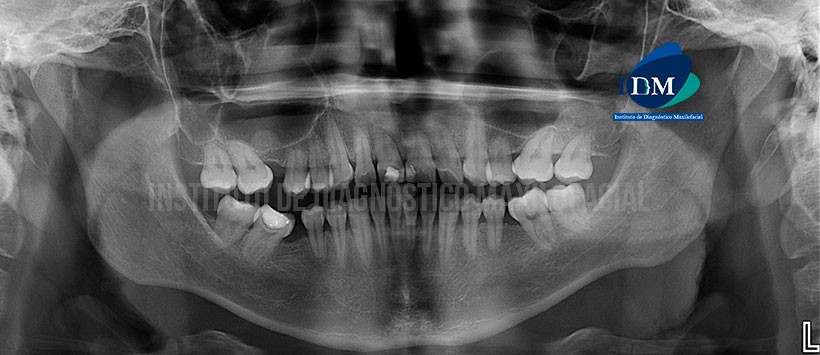

A la evaluación de la radiografía panorámica se aprecia una neumatización alveolar de ambos senos maxilares y engrosamiento de la mucosa basal de ambos senos, Disminución de la longitud radicular de todas las piezas y ausencia de la pieza 16, 25 36 y 46. (Figura 1)